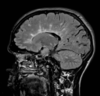

14

Q

35 anos, Masculino

A

Craniofaringioma adamantinomatoso

Craniofaringioma adamantinomatoso Crianças Lesão suprasselar com componente sólido e cístico; lobulado; calcificação anelar ou nodular presente em quase TODOS os craniofaringeomas pediátricos; Componente cístico proeminente e componente sólido pequeno, mas com realce.